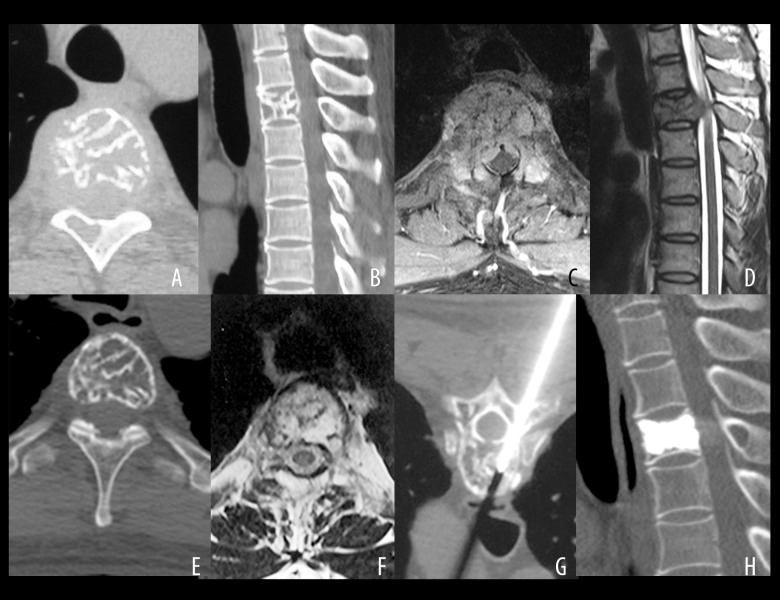

Figure 1.

Computed tomography (CT) and magnetic resonance imaging (MRI) of aggressive vertebral hemangioma (VH). (A) The typical appearance of vertebral hemangioma (VH) on axial computed tomography (CT) reconstruction. (B) The typical appearance of vertebral hemangioma (VH) on sagittal CT reconstruction. (C) The typical appearance of vertebral hemangioma (VH) on axial magnetic resonance imaging (MRI). (D) The typical appearance of vertebral hemangioma (VH) on sagittal MRI.

Figure 3.

A case of a 43-year-old man with mild myelopathy and pain for four months (Frankel grade of D) showing vertebral computed tomography (CT) and magnetic resonance imaging (MRI) and histopathology following radiotherapy for aggressive vertebral hemangioma (VH). A 43-year-old man experienced mild myelopathy and pain for four months (Frankel grade D). After percutaneous biopsy, he underwent radiotherapy with 40 Gy. Complete neurological recovery was achieved one year after radiotherapy with minor re-ossification, requiring vertebroplasty 60 months after radiotherapy because of a suspicion of a possible pathological fracture. (A) Axial computed tomography (CT) scan of an osteolytic lesion in the vertebral body and right lamina of T4. (B) Sagittal CT scan of an osteolytic lesion in the vertebral body and right lamina of T4. (C) Axial magnetic resonance imaging (MRI) showing epidural compression with vertebral canal stenosis (33.4%). (D) Sagittal MRI shows epidural compression with vertebral canal stenosis (33.4%). (E) Slight re-ossification on disappearance of epidural compression 60 months after radiotherapy. (F) Slight re-ossification upon disappearance of epidural compression 60 months after radiotherapy. (G) Negative pathology results following percutaneous biopsy and vertebroplasty. (H) Axial CT scan at the 108 months of follow-up showing no recurrence of the hemangioma.